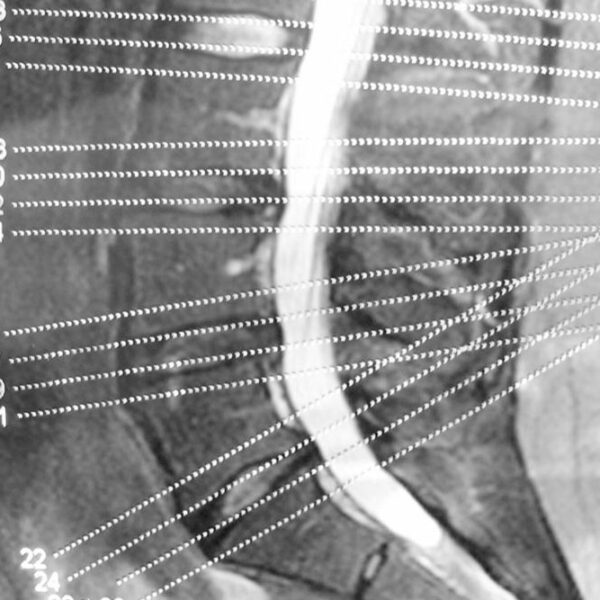

The spinal column consists of spinal discs that perform the task of providing padding between the vertebrae, i.e., the series of small bones that make up our backbone. They also act as shock absorbers and help the back remain flexible. As we age, these discs start gradually losing their elasticity property.

A common cause of this condition is the drying of your spinal discs. As you age, the water in the spinal discs dries out, flattening the spinal disc. A flattened spinal disc cannot absorb shock and they fail to provide padding to the vertebrae. Another cause of this disease can be a crack in the spinal disc. If the walls of the disc tear out, then there is a high chance that the soft core of the disc might push through the cracks and cause the disc to swell or, in the worst case, slip off.

This disease affects the facet joints, which are the joints that protect the vertebra in the spinal column from both sides. These joints make it possible for the spine to bend effortlessly.

The facet joints are lined with cartilages that cushion the joint and make sure that two adjacent vertebrae can glide smoothly against one another.